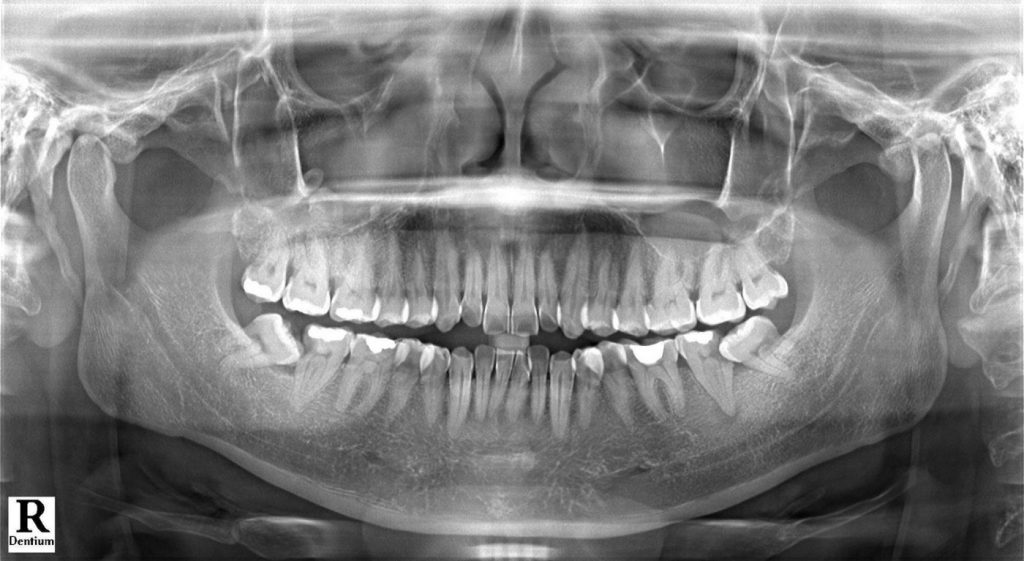

- Quy trình nhô răng khôn: khám – chụp phim (Pano/CT) – gây tê – nhổ/tiểu phẫu – khâu & hướng dẫn chăm sóc.

- Khám & chụp phim (Pano/CT Cone Beam).